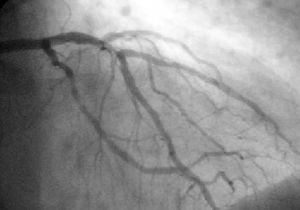

رأب الشريان التاجي

A coronary angioplasty is a therapeutic procedure to treat the stenotic (narrowed) coronary arteries of the heart found in coronary heart disease. These stenotic segments are due to the buildup of cholesterol-laden plaques that form due to atherosclerosis. A percutaneous coronary intervention is first performed.

A PCI used with stable coronary artery disease reduces chest pain but does not reduce the risk of death, myocardial infarction, or other major cardiovascular events when added to optimal medical therapy.[1]